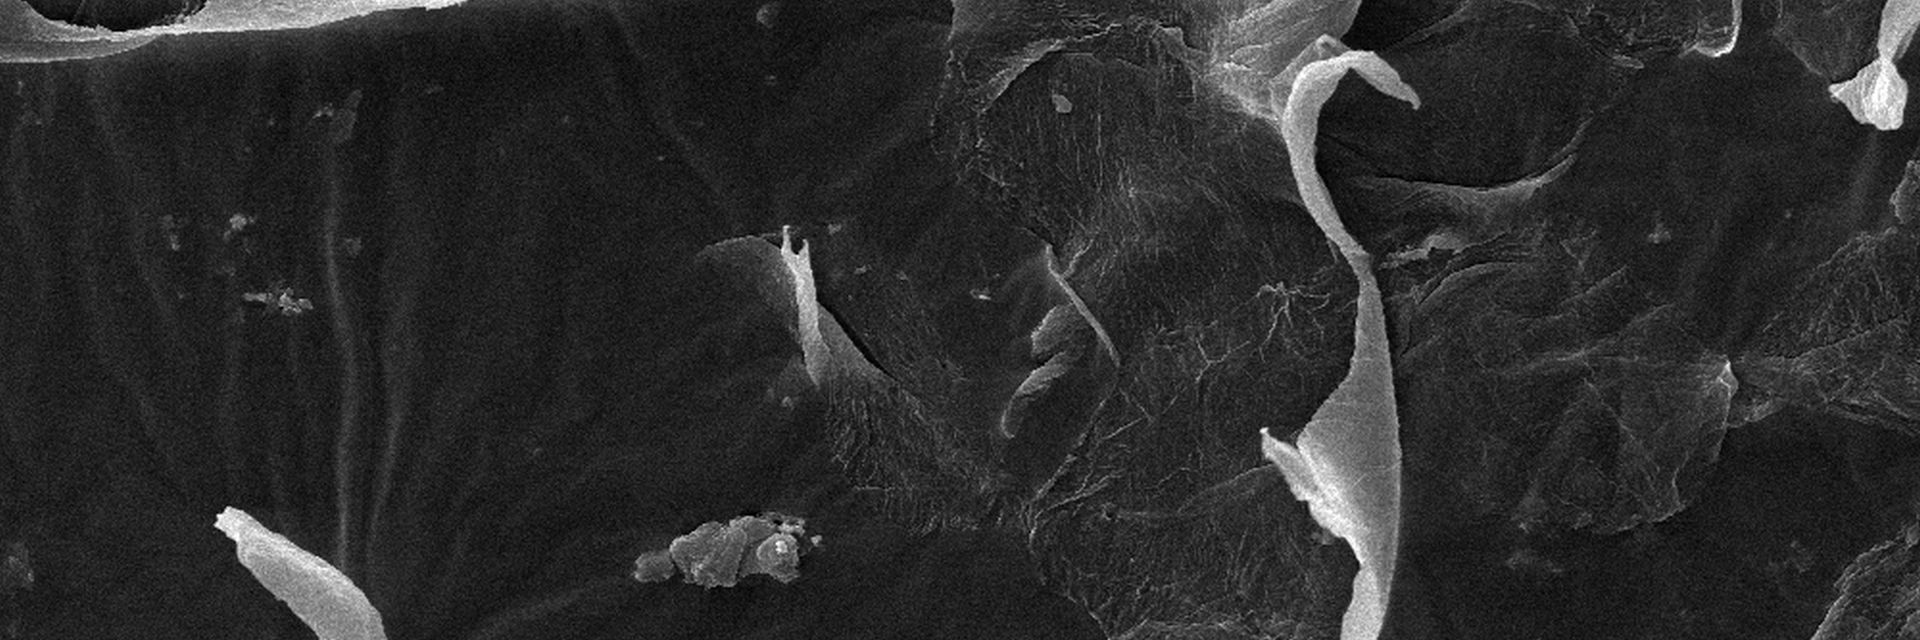

Microscopy Services setzt das patentierte Analyseverfahren Lipbarvis® (Lipid Barrier Visualisation, LBV) ein, um die epidermale Hautbarriere direkt ohne invasive Probenahmen untersuchen zu können.

Teasertext Strukturanalyse Teasertext Strukturanalyse Teasertext Strukturanalyse Teasertext Strukturanalyse Teasertext Strukturanalyse Teasertext Strukturanalyse Teasertext Strukturanalyse Teasertext Strukturanalyse Teasertext Strukturanalyse Teasertext Strukturanalyse.